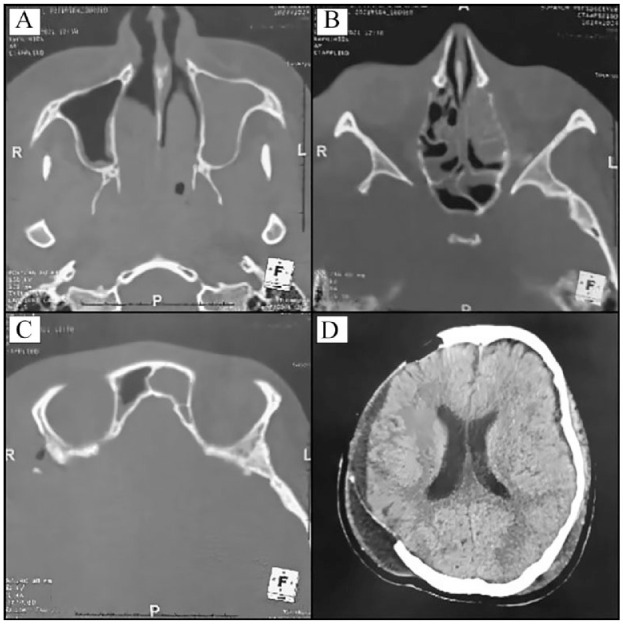

Case reports: A 22-year-old female and 30-year-old male patients, both with no significant medical history, presented with subdural empyema and intracranial epidural abscess, respectively, both complicating pan-sinusitis of dental origin. Successful outcomes were achieved with surgical drainage of the lesions, antibiotic therapy, and extraction of affected teeth. Female patient underwent further management for neurological sequelae, while male patient was discharged without neurological complications.

Abstract Image